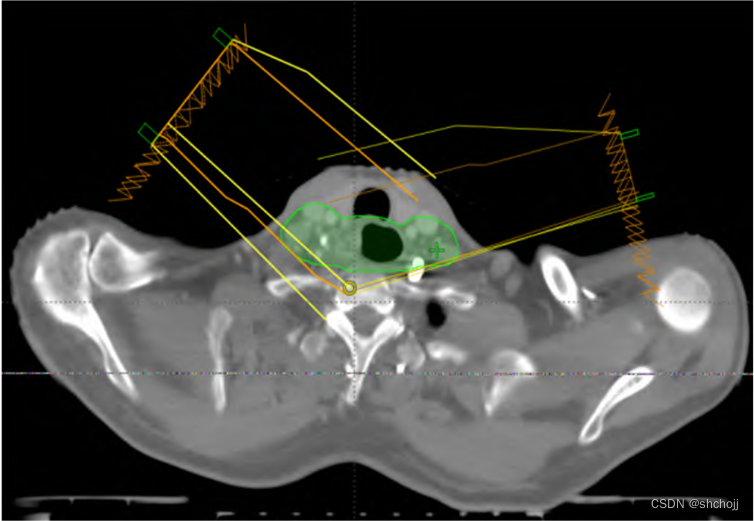

设置Block(两侧棕色区域)进行剂量约束